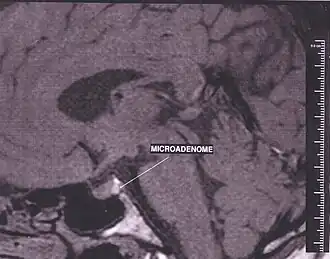

RM mózgowia z zaznaczonym mikrogruczolakiem

Na podstawie średnicy guza przeprowadzono podział gruczolaków na makrogruczolaki (≥ 10 mm średnicy) i mikrogruczolaki (< 10 mm średnicy).